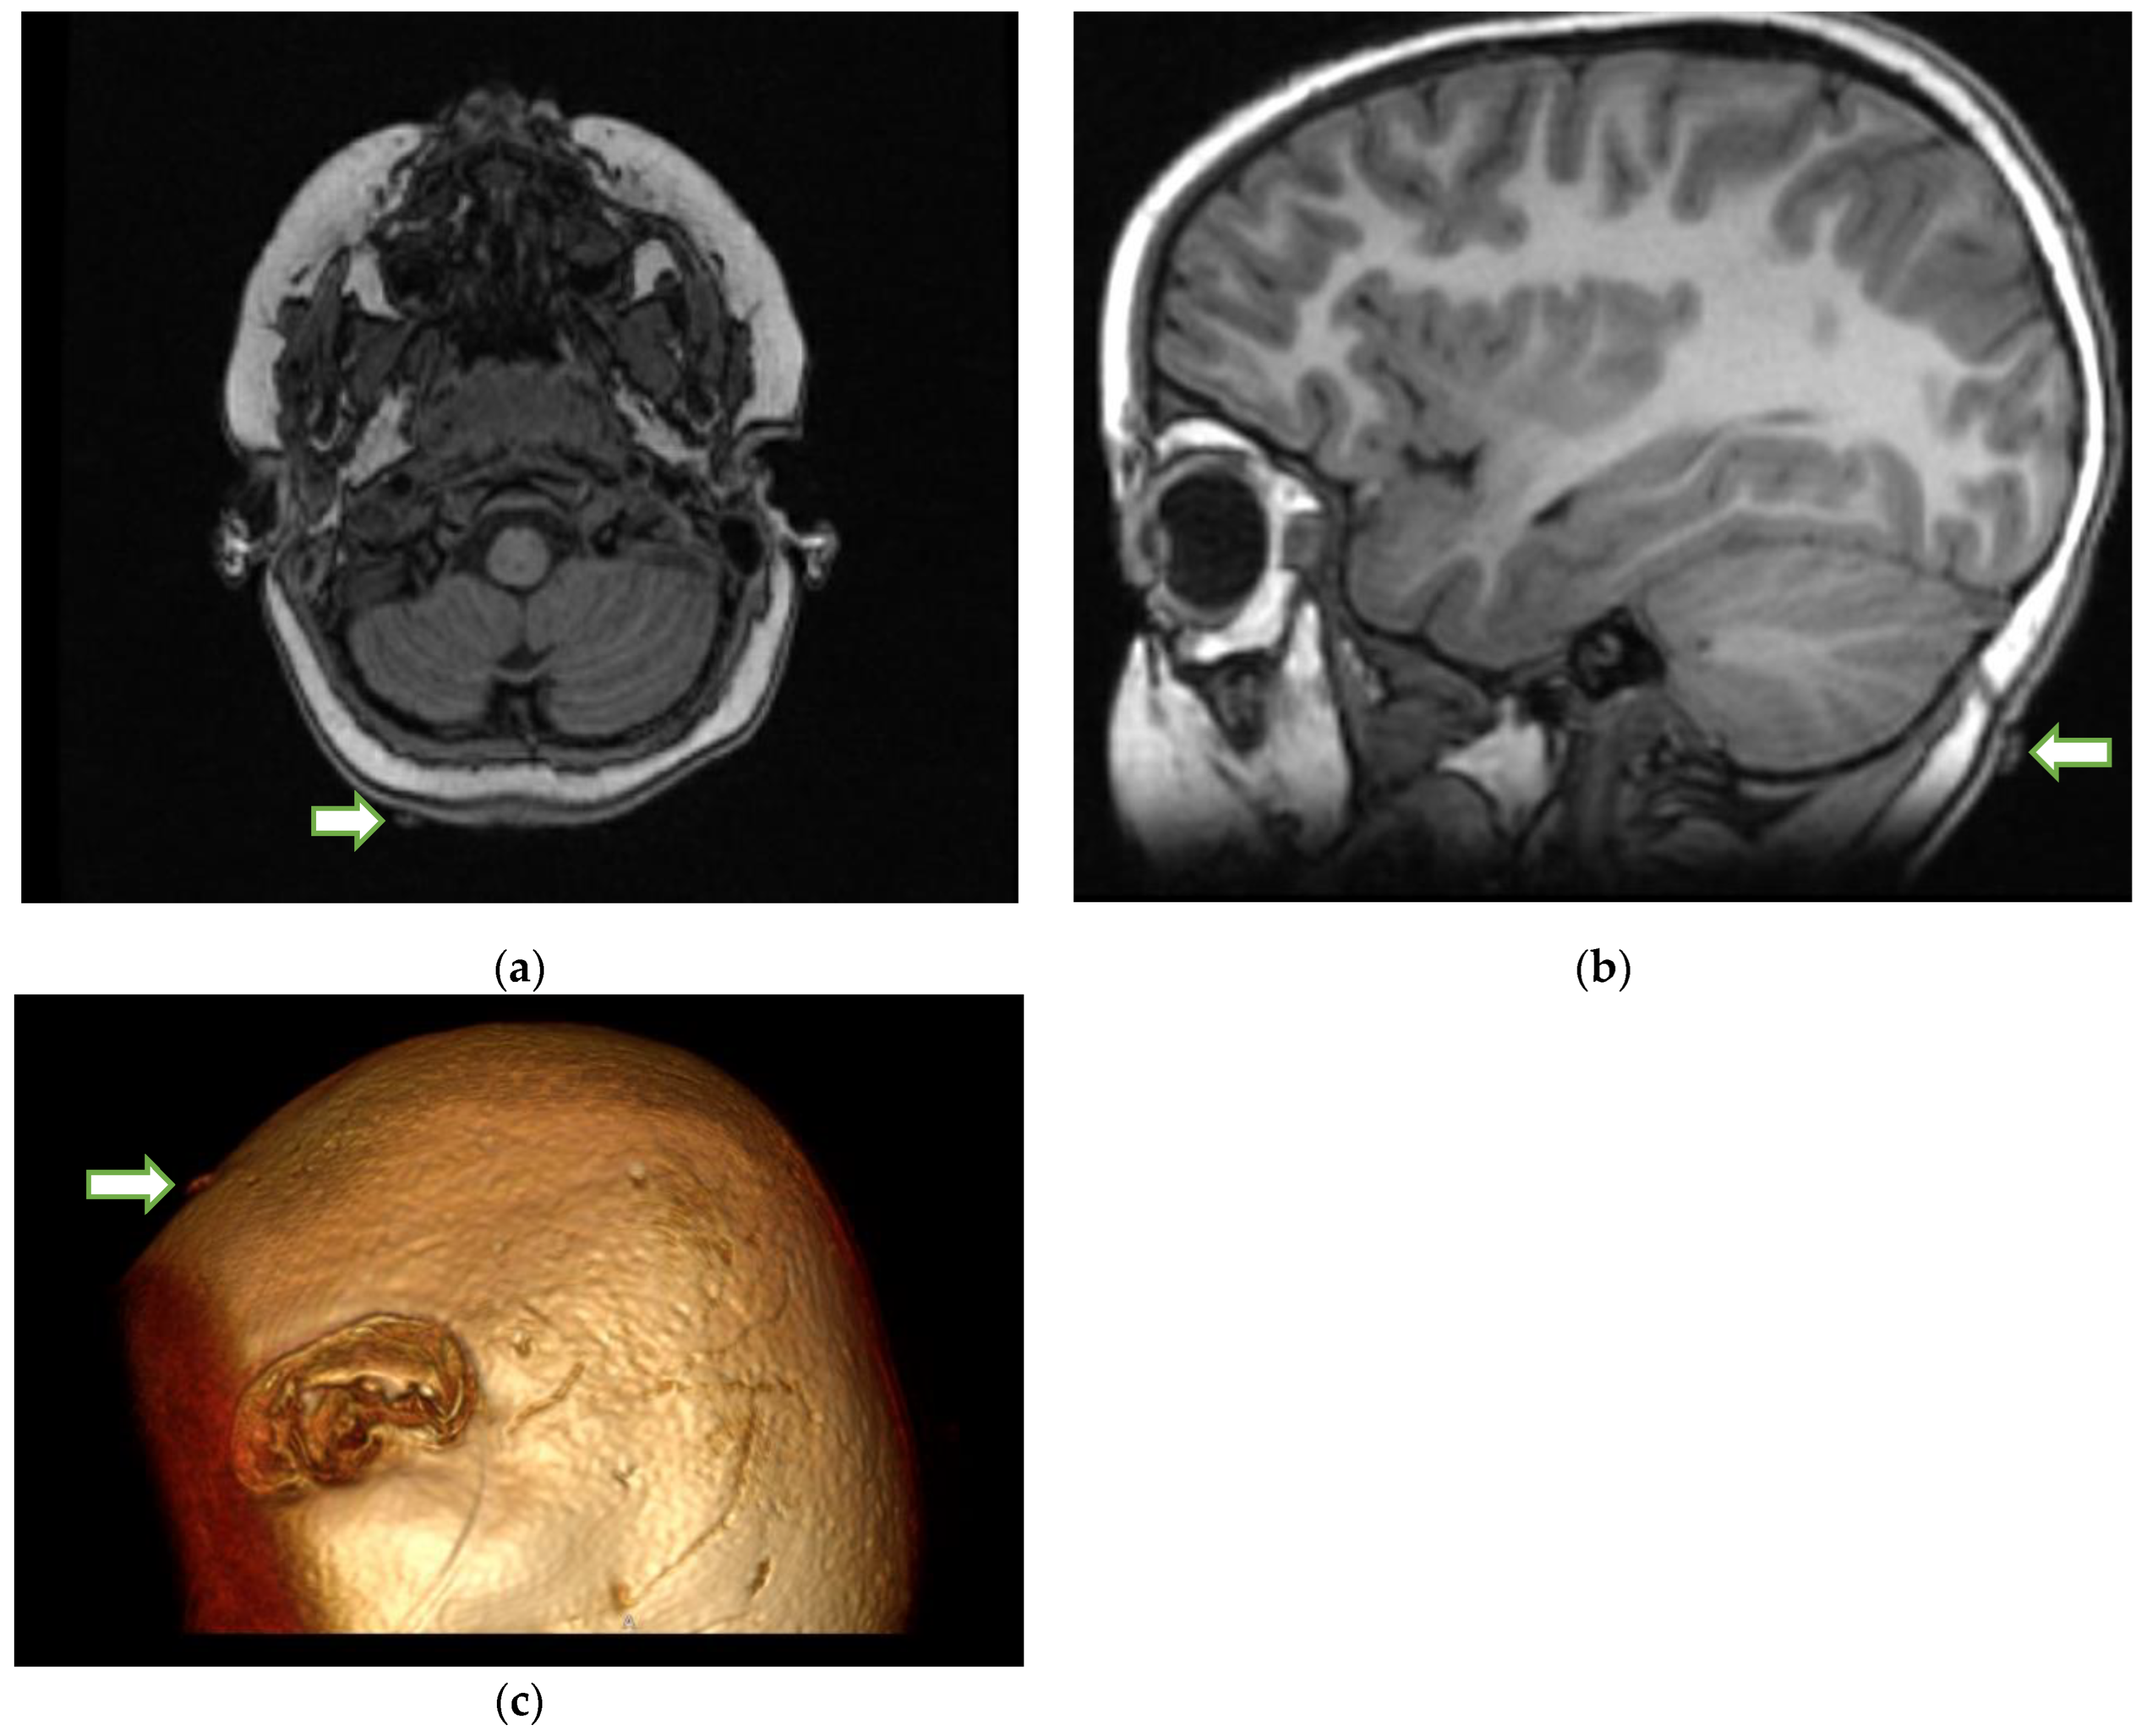

The patient’s condition deteriorated over the next 2 days, with increasing weakness and difficulty in respiration requiring intubation. Plasmapheresis was also initiated. Two days after admission, a large, engorged tick was found by the mother (Figure 1) on the posterior aspect of the patient’s scalp under a clump of deeply matted hair. It was promptly removed, and doxycycline was initiated. Her condition quickly improved after the removal. She was extubated and started on BiPap within two days of the tick’s removal. The patient was discharged from the hospital 7 days after the tick’s removal.

Figure 1. Engorged tick on the hairline.